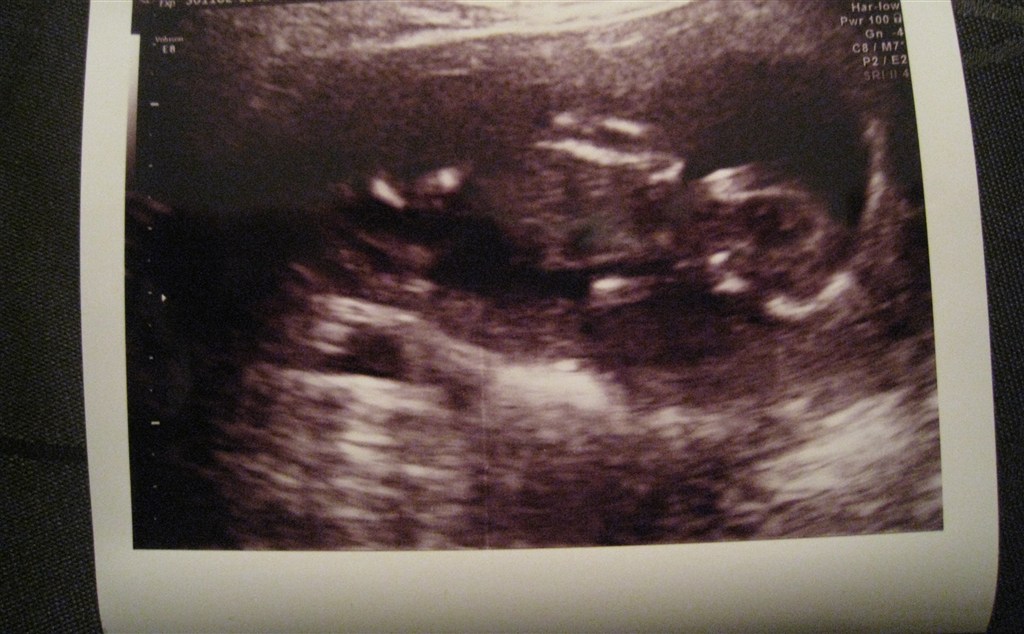

Ja sikke en nærmest uvirkelig forandring der er sket fra vores tidlig scanning i uge 8 og så frem til nu i uge 13.. Efter idag, må jeg simpelthen bare begynde at tro på det, sådan rigtig og for alvor..

Blev selv scannet da jeg var 9+0 hvor det bare var en lille "reje" og til nf da jeg var 12+2 var det en lille baby med arme og ben, og ører på vej..